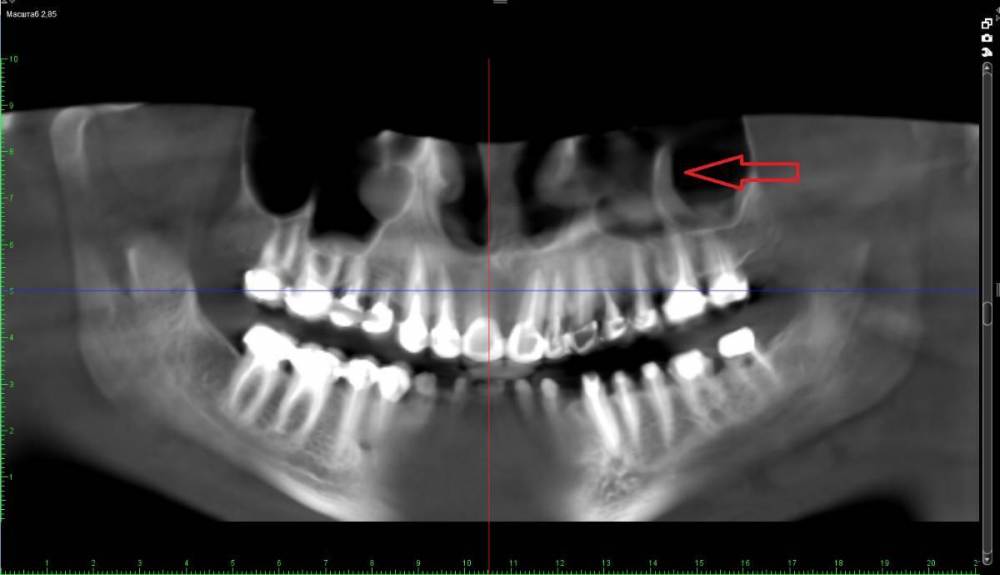

neumann Опубликовано 24 марта, 2022 Поделиться Опубликовано 24 марта, 2022 Добрый день. После перелечивания каналов 6 зуба появились неприятные ощущения в пазухе и слева от глаза. Сделали КТ и вот что оно показало. Нужно ли бить тревогу (см. указатель) или в этом нет ничего страшного? На что еще нужно обратить внимание? Спасибо. Ссылка на комментарий

Женька Опубликовано 24 марта, 2022 Поделиться Опубликовано 24 марта, 2022 Нужны срезы КТ, а не реформат ОПТГ. Ссылка на комментарий

Женька Опубликовано 24 марта, 2022 Поделиться Опубликовано 24 марта, 2022 @neumann уже что-то теперь нужны срезы именно "вокруг" этого зуба На первый взгляд это просто анатомическое образование. Так называемая септа (перегородка) в верхнечелюстной пазухе. И повода для беспокойства нет (если судить именно по тем срезам что Вы предоставили. Ссылка на комментарий